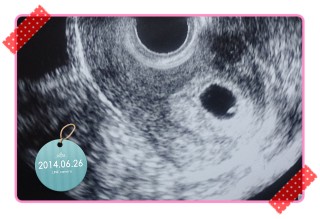

ちゃんと着床してたよーっ!小さな点が、赤ちゃんに栄養を与えている袋だよ!と…言われました。 着床出血があり、えーーっ!と、ビックリしましたが、無事だったようです。その後、出血もなく…あと、2週間後が楽しみすぎるー! 早く心拍確認したいです! いまのところ、つわりはない感じですが…胸焼けが少しある気がする…